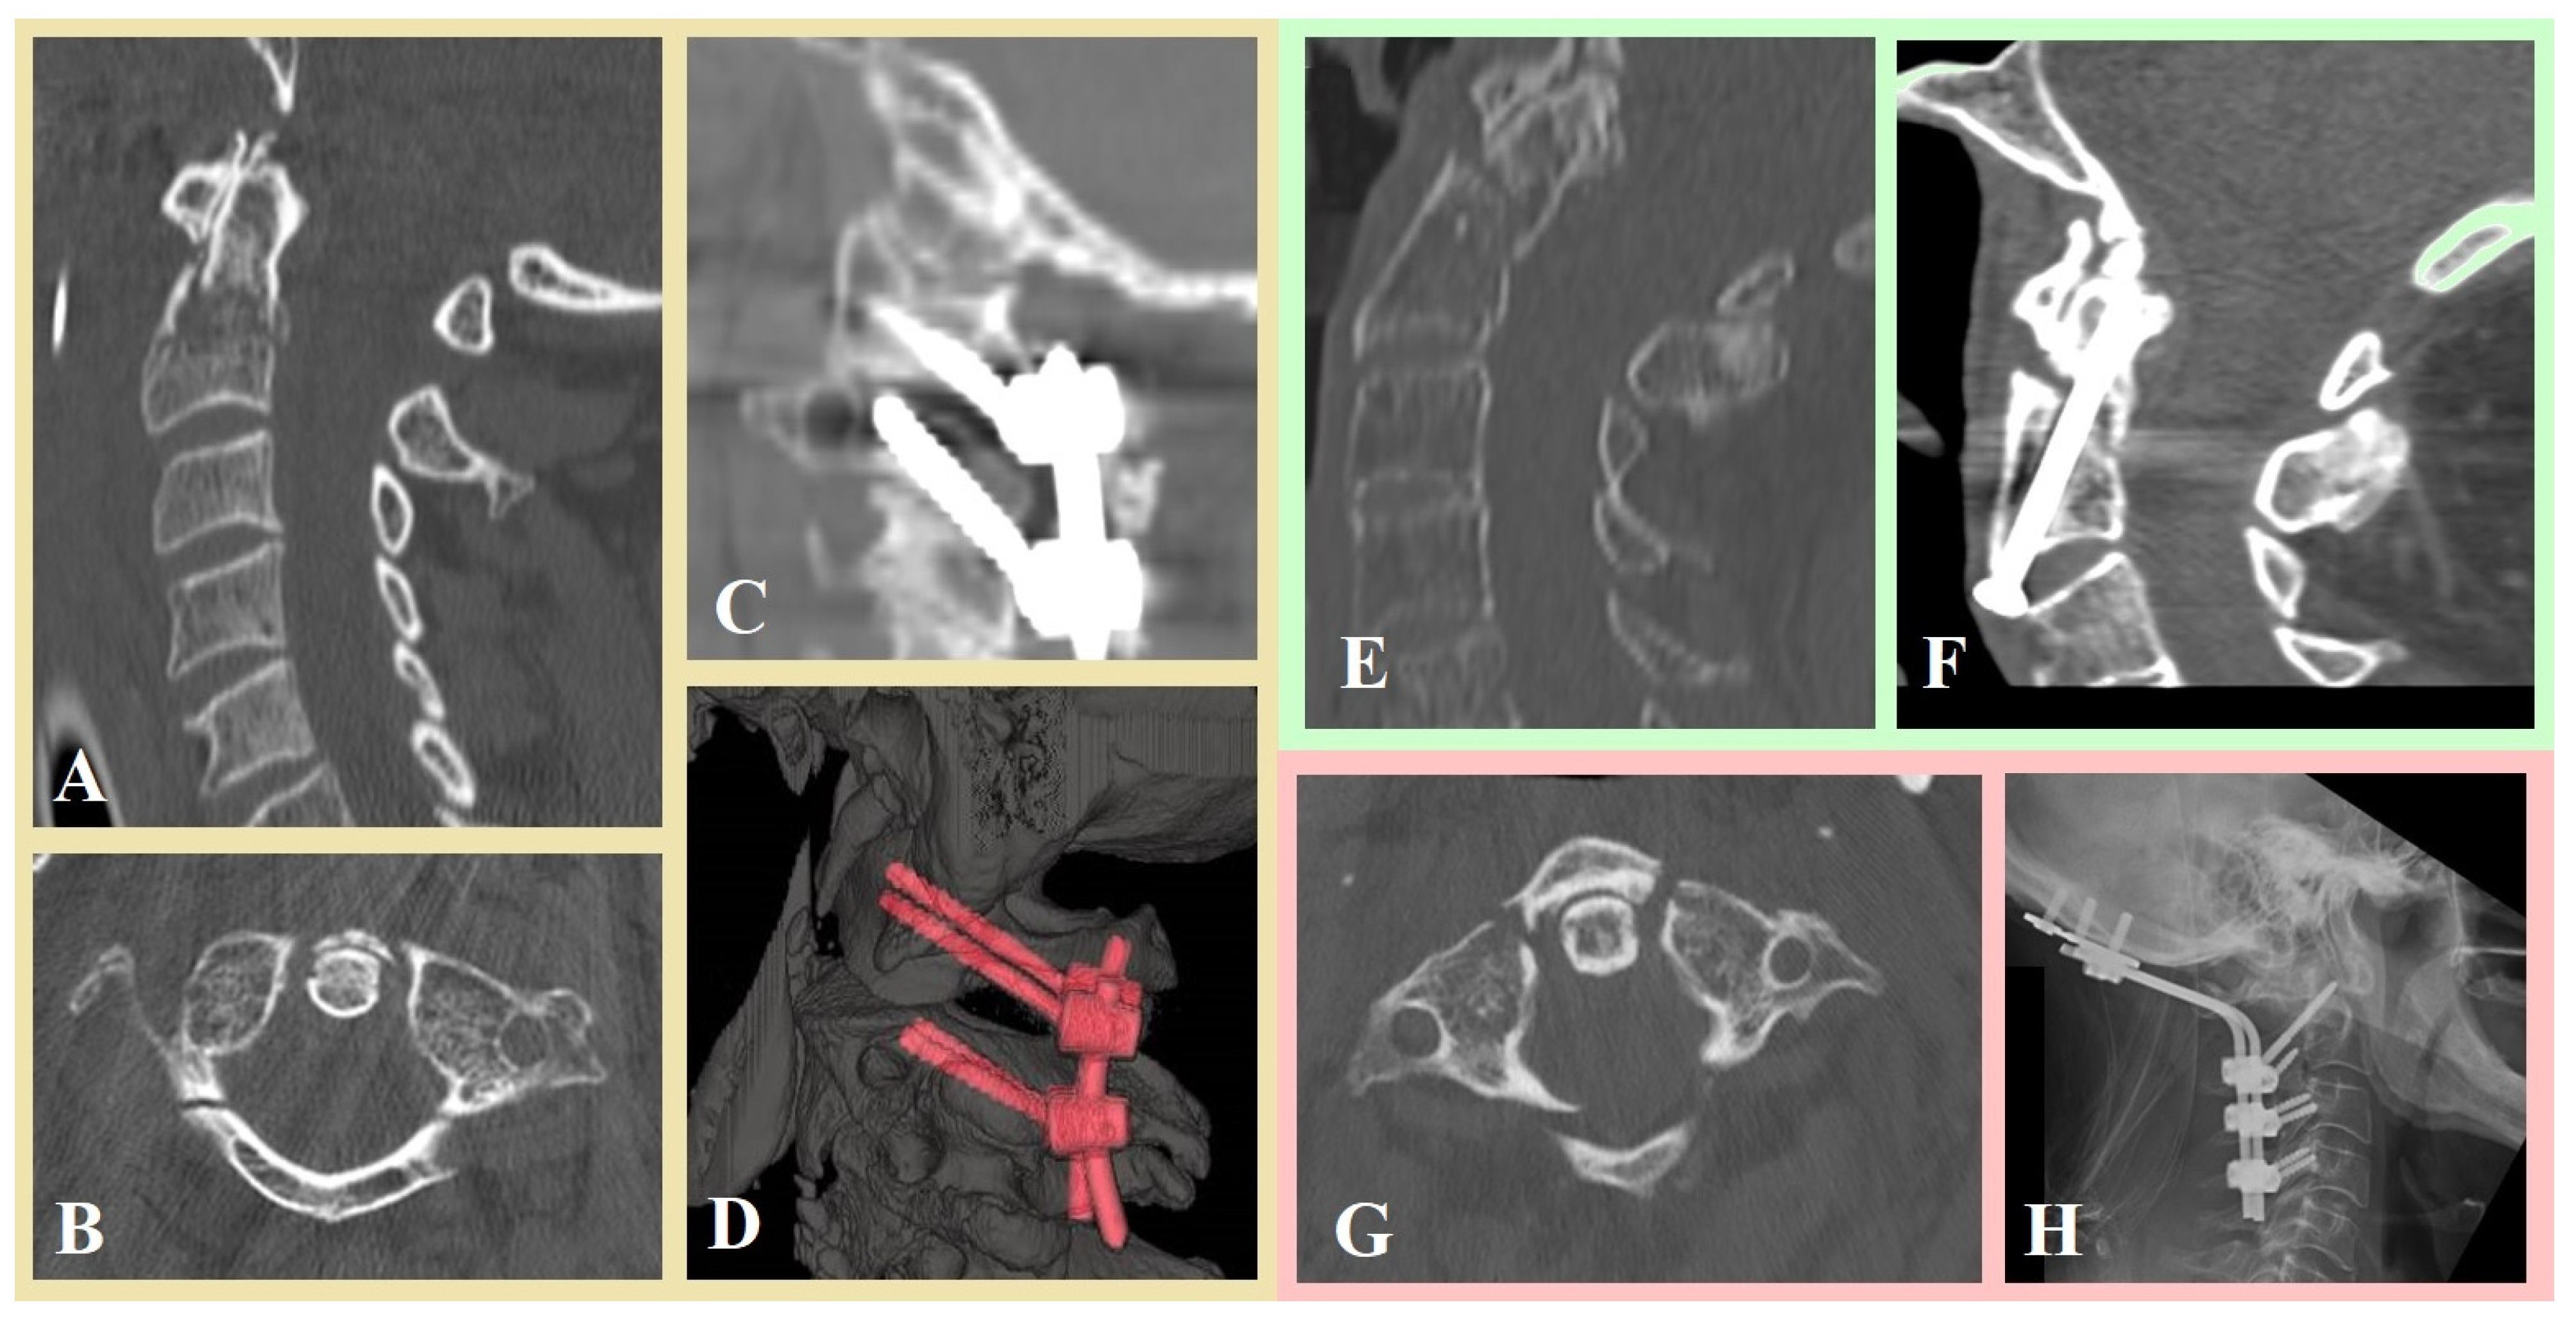

| Surgical treatment | 74 (100) |

| C2 dens screwing | 22 (29.7) |

| C2–C3 discectomy and fixation with plate | 8 (10.8) |

| Occipitocervical fixation | 11 (14.9) |

| C1–C2 fixation Harms technique | 25 (33.8) |

| C1–C2 fixation Magerl technique | 8 (10.8) |